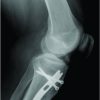

A 26-year-old male accountant by profession presented to our outpatient department with complaints of sudden onset right knee. The pain started after a motor bike ride 2 weeks back and while he reported some relief with anti-inflammatory drugs, the pain kept recurring, and got precipitated with any deep flexion activity including stair climbing. He also reported locking episodes. Further detailed history revealed that the patient sustained penetrating trauma to the right knee 14 months back. Glass shard pierced anterolateral aspect of the knee due to direct impact over the glass door. Patient was immediately taken to local hospital and penetrated glass shard was removed under sedation. As per the patient, local wound exploration was meticulously executed and primary closure performed following thorough wash and debridement. The wound healed by primary intention and patient was able to resume activities of daily within 2 weeks. The only radiological investigation done at the time was the X-rays and they were reported to be not suggestive of bony injury. 6 months after the index injury patient still had a sense of feeling something inside the joint and experienced pain during ground level activities. Patient visited again in view of the complaints and re-exploration was performed from the previous scar. A small glass piece was retrieved anew from the deeper extra-articular tissue as evident from the history narrated by the patient. No further investigations were advised. Patient was assured regarding complete removal of the glass fragment and was sent home. Patient was absolutely fine till few days back he experienced sudden onset excruciating pain in the right knee after bike ride. With this background, patient came to us with apparently normal looking knee and healed scar of around 5 cm over anterolateral aspect of the right knee. Clinical examination was not suggestive of any significant ligamentous injury. Tenderness was elicited over deep flexion. Radiographs done at this time did raise a suspicion of possible foreign body in notch area (Fig. 1). Computed tomography (CT scan) was advised with suspicion of remnant glass shard inside the joint and delineate the topographic location with respect to the joint. CT scan revealed hyperdense foreign body within the joint measuring approximately 15*6 mm situated anterior to lower one-third of anterior cruciate ligament (ACL) (Fig. 2). Patient was posted for arthroscopic retrieval of the foreign body after anesthetic evaluation and was also consented for a possible open exploration.